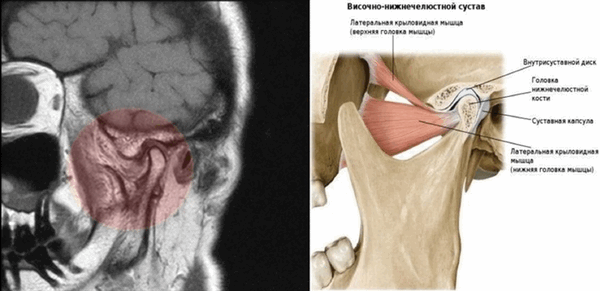

МР-снимок ВНЧС и анатомия сочленения

Перед МРТ не нужна специальная подготовка. Пациенту разрешено принимать пищу. В случае, если делается усиленное сканирование, легкий перекус за 40-45 минут поможет уменьшить признаки активации вегетативной нервной системы после введения препарата (повышенное отделение слюны, чувство жара, головокружение). Советуем подойти к кабинету за 10-15 минут, чтобы не торопясь снять все металлические предметы (серьги, заколки и пр.). Последнее нужно, чтобы изображения не исказились и были информативными.